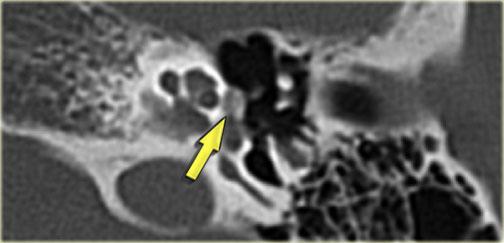

Bên trái là hình ảnh hành tĩnh mạch cảnh hở (mũi tên xanh dương).

Đây có thể là một nguy cơ nguy hiểm trong quá trình chích màng nhĩ.

Lưu ý thêm hình ảnh xoang sigma phồng lồi (mũi tên vàng).